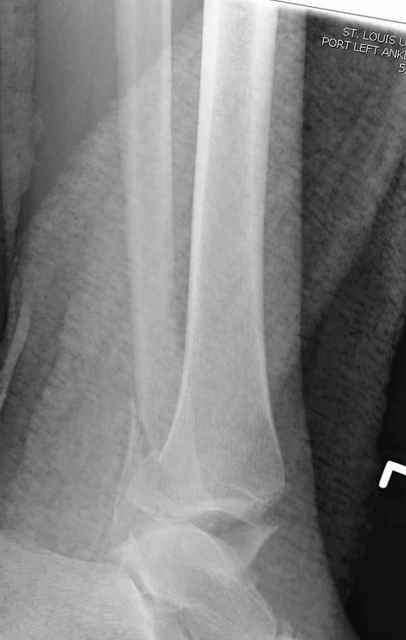

Из работ Ramsey and Hamilton, Yablon et., укорочения на 1мм

малоберцовой кости, уменьшает на 42% контактную поверхность между

малоберцевой и таранной кости, которое в свою очередь приводит к

увеличению давления на остальные части суставной поверхности, что

является предпосылкой раннего артроза.

The unsatisfactory clinical results sometimes associated with slight widening of the ankle mortise and 42% reduction in the area of contact

between the tibia and talus with one millimeter of lateral displacemet emphasize the importance of restoring the normal roentgenographic relationship of the talus to medial malleolus after ankle

injures. Since the stress per unit area increases as the total area decreases, a decrease in contact area may be a factor contributing to a poor result after ankle or dislocation when talar displacement is one millimeter or more.